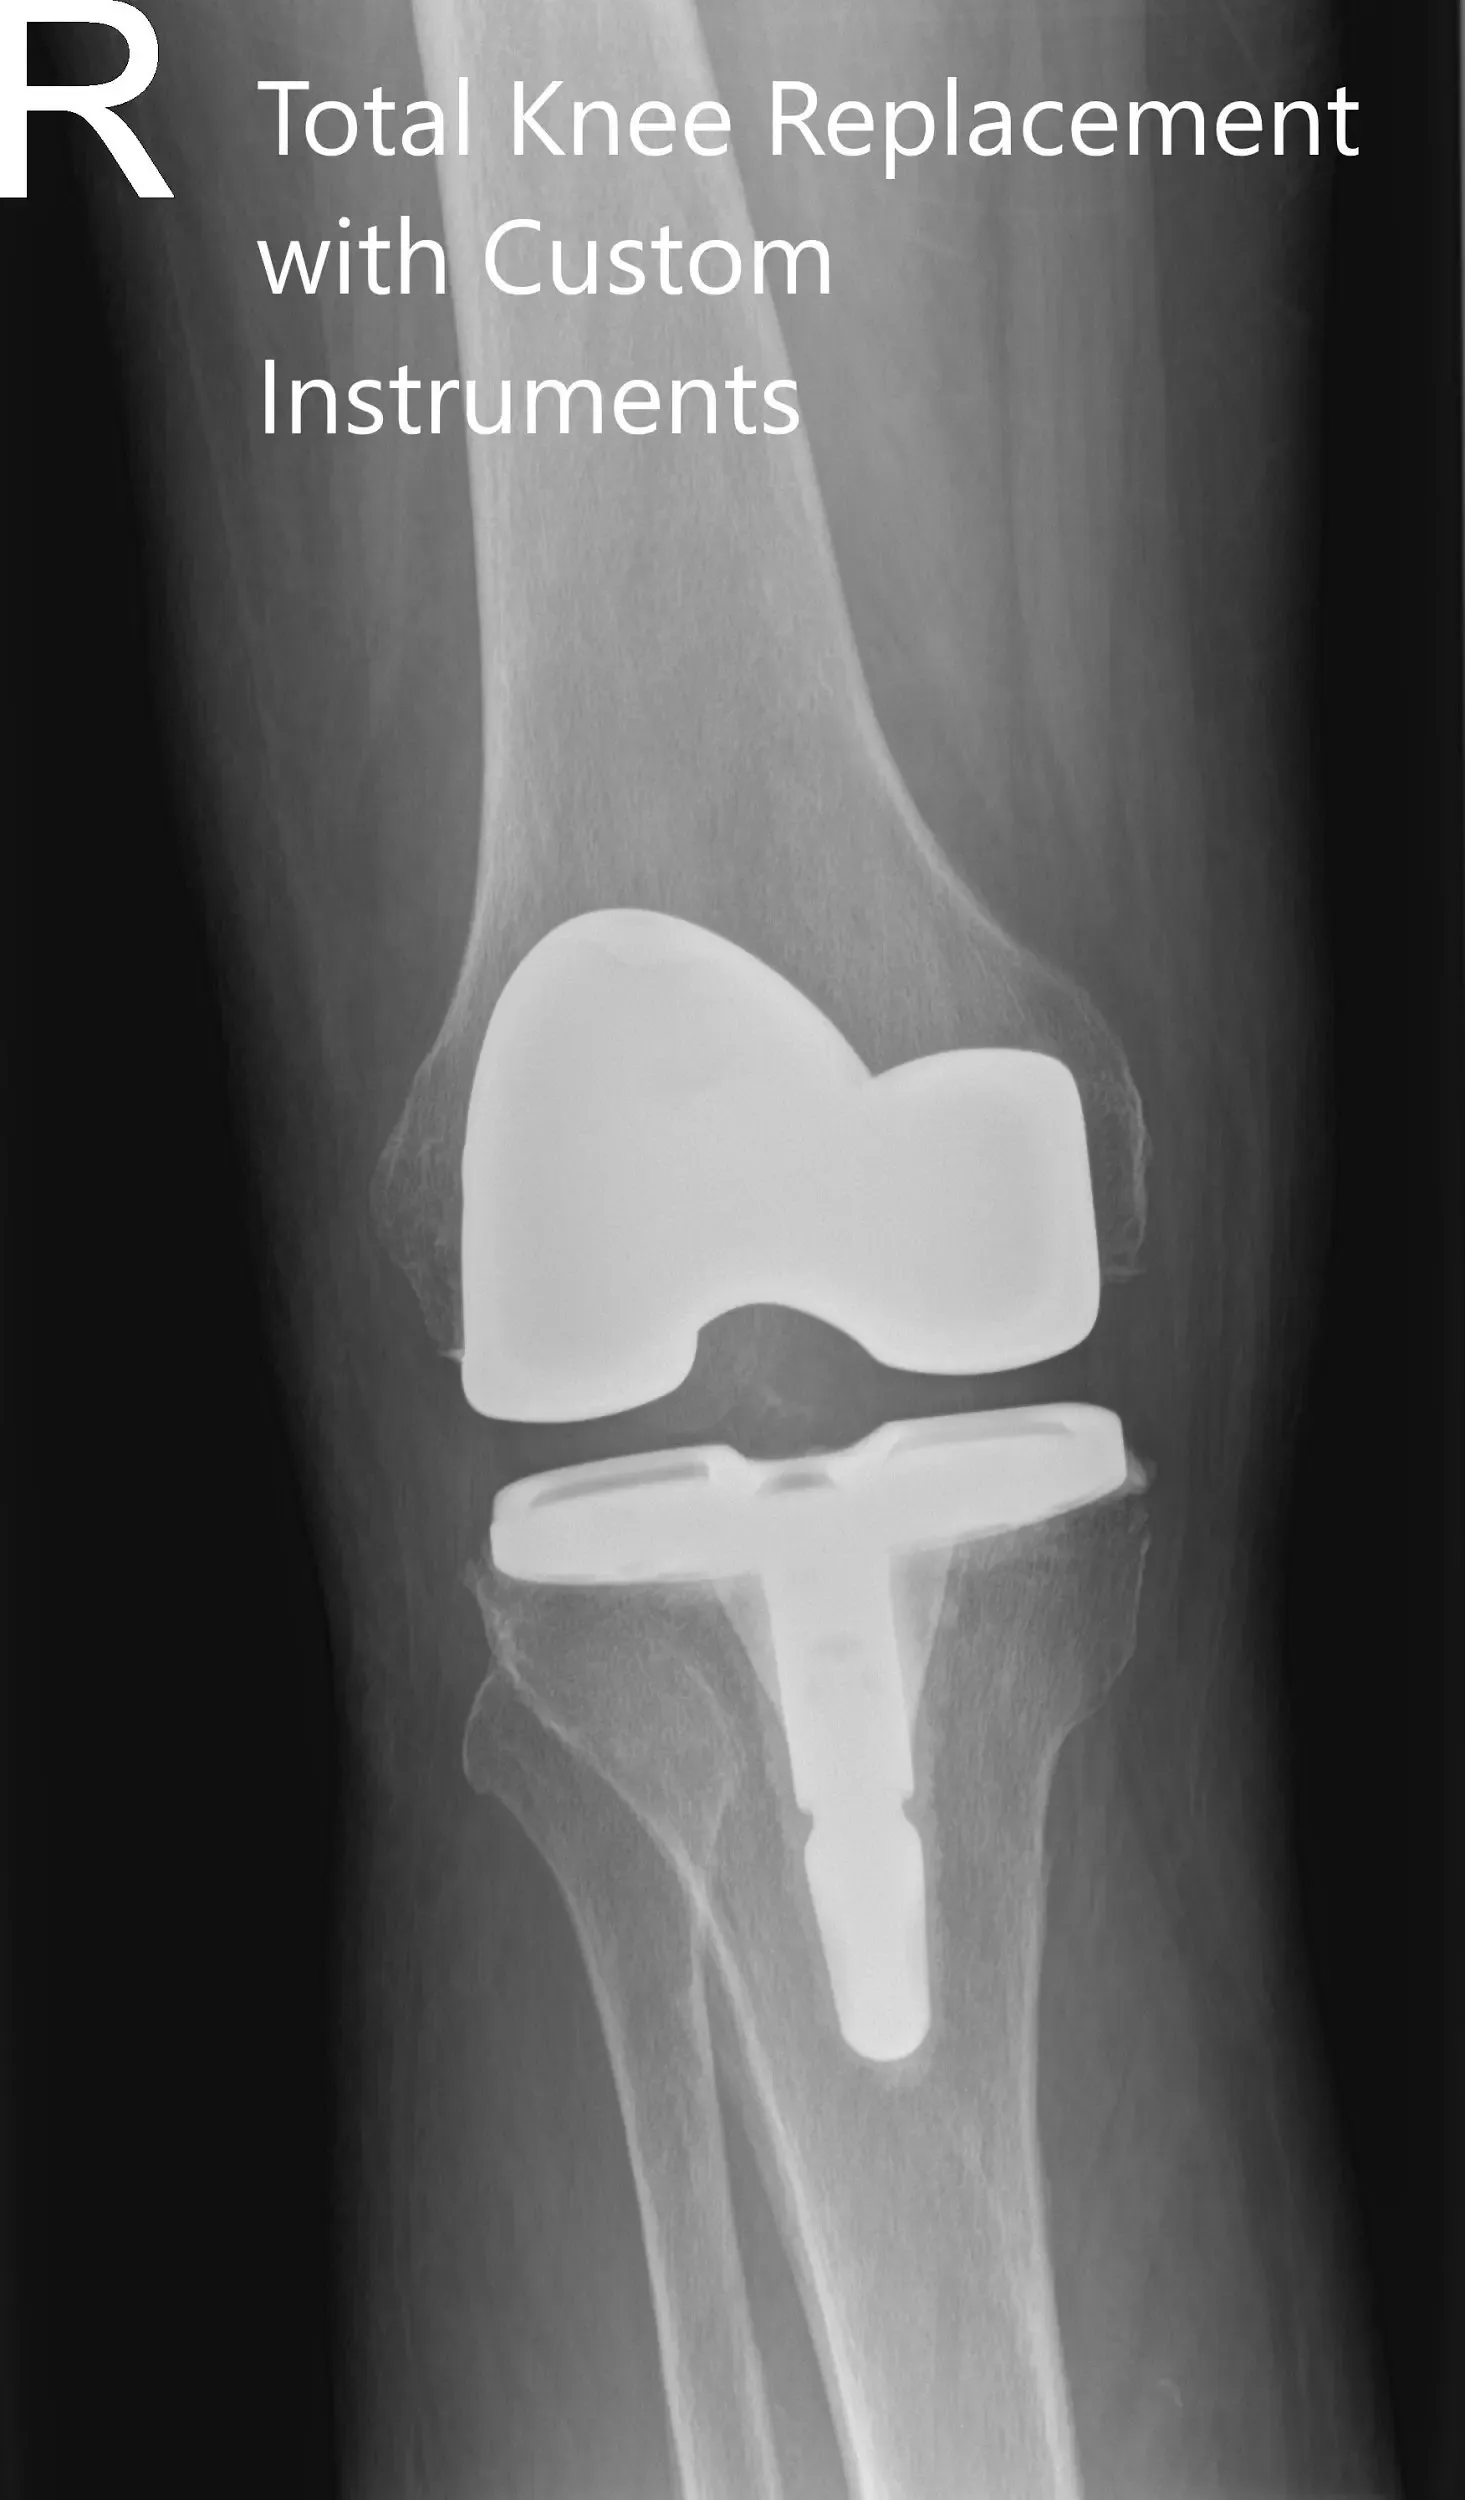

IMPLANTES UTILIZADOS: Estabilización posterior, 10 componentes femorales estándar derecho lado derecho con tibia F izquierda cementada con tallo de 14 x 30 y poli de 16 mm y una rótula polirótula de 32 x 8,5 mm de diámetro.

Radiografía postoperatoria de la rodilla derecha en vistas anteroposterior y lateral.